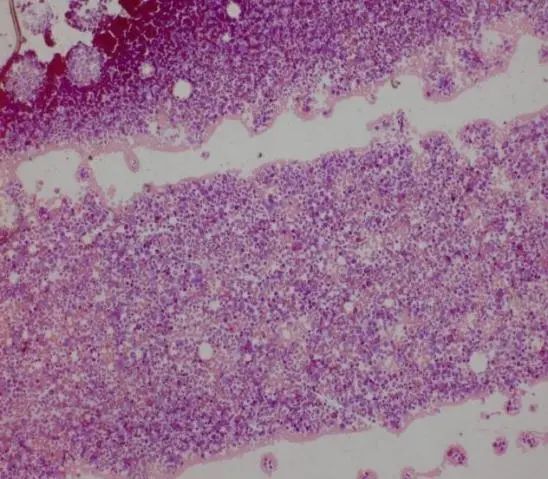

5、骨髓活检:骨髓增生明显活跃,粒系比例明显增高,红系比例减低,巨核细胞不少。网状纤维染色:MF-1。见图9。

图片

图9 骨髓活检结果截图

骨髓活检分析:

1、骨髓活检网状纤维轻度增多,中性粒细胞明显增高,需要排除MF(MF加速期可有中性粒细胞明显增多表现);PMF的特征是骨髓中异常巨核细胞和粒细胞增生,纤维化期与成纤维细胞的多克隆增加相关,这导致继发性网状纤维和/或胶原纤维增生性骨髓纤维化、骨硬化和髓外造血。本例中不存在三系增生异常情况,尤其是巨核细胞系,并无小巨核、及成簇分布的小巨核等。

2、轻度网状增多可继发于感染、自身免疫性疾病、其他慢性炎症、毛细胞白血病、转移性肿瘤等。

3、无诊断PMF主要标准之一的JAK2、CALR以及MPL基因突变(三阴),因此PMF暂不考虑,网状纤维轻度增多多考虑继发性MF。

4、尚需要检测ASXL1、EZH2、TET2、IDH1/2、SRSF2、SF3B1等提示疾病克隆性的的伴发突变基因。

本例虽然持续性外周血中性粒细胞增多,但以成熟阶段细胞为主,未见幼粒细胞、幼红细胞等,无脾脏肿大等临床表现,结合基因等检查基本排除MF可能。